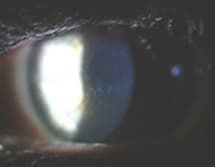

This photo shows the cornea of a 19-year-old female who initially presented with binocular ocular pain and photophobia that was more severe in the right eye. Her accompanying signs included bilateral pre-auricular adenopathy, follicular hypertrophy, multiple corneal infiltrates, and conjunctival injection. All of these presentations were more pronounced in the right eye. We diagnosed viral keratoconjunctivitis and instructed the patient to discontinue contact lens wear, initiate a treatment regimen of tapering topical steroid therapy, and return in one week for evaluation.

The patient did not keep her subsequent appointment, but three weeks later she again presented with similar symptoms. Visual acuity was reduced to 20/30 in the right eye and her clinical presentation was as it appears in this photo.